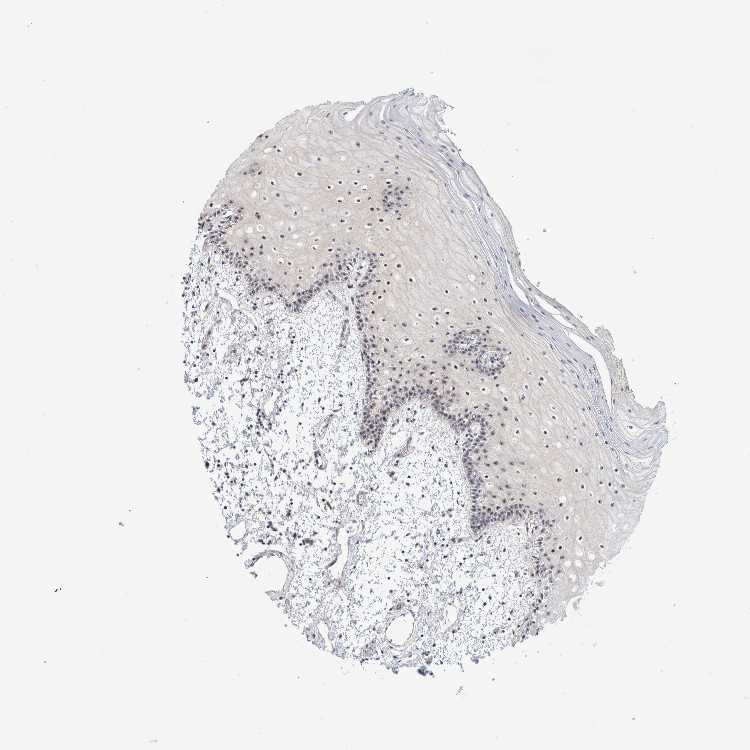

TISSUE PRIMARY DATA ORAL MUCOSA Show tissue menu

ORAL MUCOSA - Antibody stainingi

Antibody staining in the annotated cell types in the current human tissue is reported as not detected, low, medium, or high, based on conventional immunohistochemistry profiling in selected tissues. This score is based on the combination of the staining intensity and fraction of stained cells.

Each image is clickable and will lead to virtual microscopy that enables deeper exploration of all samples and also displays staining intensity scores, fraction scores and subcellular localization as well as patient and tissue information for each sample.

Antibody HPA022010

Squamous epithelial cells High